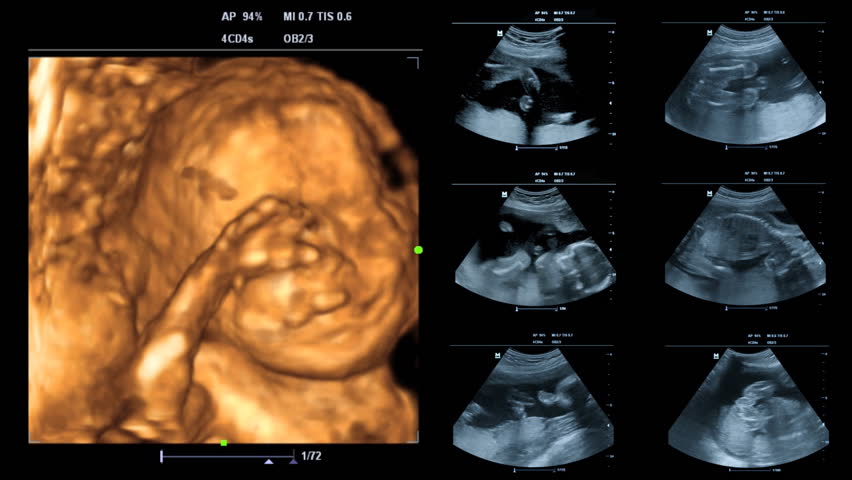

22 недели видео

22 недели видео 114 фото